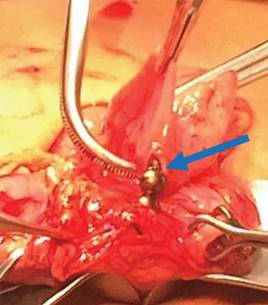

Se toma nueva radiografía de abdomen observando seis imanes más (Figura 5). Por sospecha de perforación, se realiza laparotomía exploradora encontrando que el epiplón cubre al estómago y al retirarlo se observa asa de intestino delgado pegada a la curvatura mayor del estómago. Al despegar el asa se aprecia un orificio en el intestino (localizado a 30 cm de la válvula ileocecal), el cual comunica con otro en el estómago. En esta porción intestinal se observan los seis imanes restantes (Figura 6). Se realiza resección de 6 cm de íleon con anastomosis término-terminal y en estómago se reavivan los bordes cerrando en dos planos. Se maneja con ayuno por cinco días, sonda nasogástrica, triple esquema antibiótico, omeprazol y analgésicos. La evolución es satisfactoria y se egresa a los siete días. Se le da seguimiento por seis meses permaneciendo asintomática.